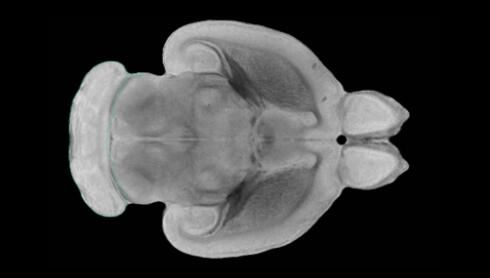

隨著機體年齡增加,肌肉和關(guān)節(jié)都會變得僵硬,這就會使得日?;顒幼兊酶永щy,本文研究表明,我們的大腦也是如此,與年齡相關(guān)的大腦僵硬對大腦干細胞的功能或許有著重要影響。文章中,研究人員對年輕和老化大鼠的大腦進行研究闡明了年齡相關(guān)大腦僵硬對少突膠質(zhì)前體細胞(OPCs,oligodendrocyte progenitor cells)功能的影響。OPCs是一類對維持正常大腦功能非常重要的大腦干細胞,其對于髓磷脂的再生也非常重要,髓磷脂是神經(jīng)組織周圍的脂肪鞘,在多發(fā)性硬化癥中髓磷脂的再生常常會被損傷,機體老化對這些細胞的影響常常會誘發(fā)多發(fā)性硬化癥的發(fā)生,這些細胞的功能在老化的健康人群中同樣會下降。

為了確定老化OPCs的功能缺失是否可以被逆轉(zhuǎn),研究人員將來自老化大鼠機體的老化OPCs轉(zhuǎn)移到了年輕大鼠柔軟的海綿狀大腦組織中去,值得注意的是,這些老化的大腦細胞能夠重新恢復(fù)活力,其行為非常像年輕更加強壯的細胞。這項研究中,研究人員在實驗室中開發(fā)出了具有可變僵硬程度的新型材料,并在受控環(huán)境下研究這些材料的生長及其對大鼠大腦干細胞的影響,這些材料能被工程化改造具有和年齡或老化大腦相似的柔軟程度。

為了深入理解大腦組織柔軟和僵硬影響細胞行為的分子機制,研究人員對細胞表面一種名為Piezo1的蛋白質(zhì)進行了分析,該蛋白質(zhì)能“告知”細胞其周圍的環(huán)境為柔軟或僵硬。研究者Kevin Chalut說道,我們發(fā)現(xiàn),當在僵硬材料上促進年輕具有功能性的大鼠干細胞時,這些細胞就會表現(xiàn)出功能異常,并失去其再生的能力,實際上其行為與老化細胞相似。當將老化的大腦細胞在柔軟材料上生長時,其功能就會表現(xiàn)得像年輕細胞一樣,換句話說,其能夠重新恢復(fù)年輕的活力。